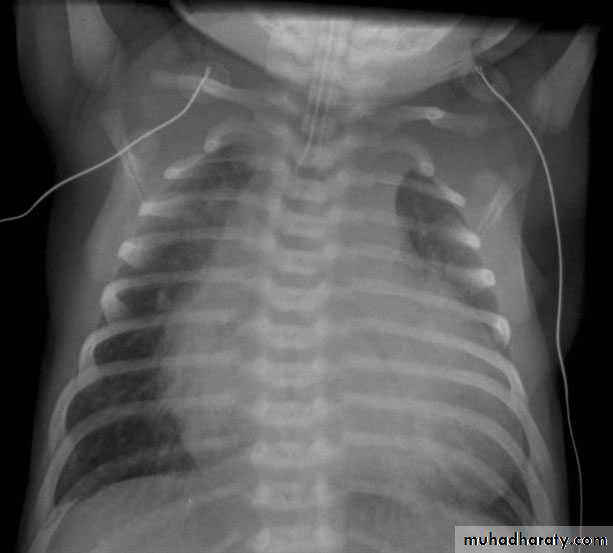

CXR

Size of the heart is difficult to determine radiologically, particularly if there is a superimposed thymic shadow.

Enlarged cardiac shadow unassociated with signs of CHF- suspect that shadow noncardiac

Absence of cardiomegaly in a good inspiratory film (with diaphragm near the 10th rib posteriorly) practically excludes CHF except due to a cause like obstructed total anomalous pulmonary venous connection (TAPVC)

CT Ratio method, > 60%

Massive cardiomegalyRA dilation

Pulm plethora

LV Dialatation